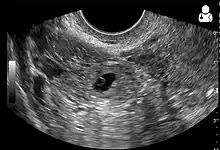

An ultrasound showing a gestational sac with fetal heart in the fallopian tube has a very high specificity of ectopic pregnancy. Transvaginal ultrasonography has a sensitivity of at least 90% for ectopic pregnancy.[4] The diagnostic ultrasonographic finding in ectopic pregnancy is an adnexal mass that moves separately from the ovary. In around 60% of cases, it is an inhomogeneous or a noncystic adnexal mass sometimes known as the "blob sign". It is generally spherical, but a more tubular appearance may be seen in case of hematosalpinx. This sign has been estimated to have a sensitivity of 84% and specificity of 99% in diagnosing ectopic pregnancy.[4] In the study estimating these values, the blob sign had a positive predictive value of 96% and a negative predictive value of 95%.[4] The visualization of an empty extrauterine gestational sac is sometimes known as the "bagel sign", and is present in around 20% of cases.[4] In another 20% of cases, there is visualization of a gestational sac containing a yolk sac or an embryo.[4] Ectopic pregnancies where there is visualization of cardiac activity are sometimes termed "viable ectopic".[4]

A pregnancy not in the uterus.[31]